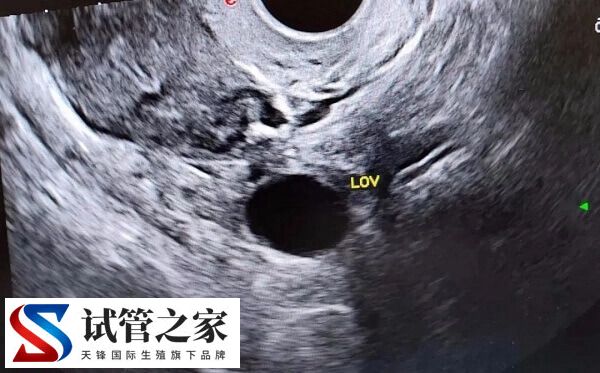

打完绒促针后仍然要做b超检测排卵情况,打针以后,有的人会出现腹水、肚子疼、卵巢过度刺激症等一些并发症,所以要密切观察有没有一些不舒服的表现。任何症状都没有的,第二天要做b超看看卵泡是否破了。